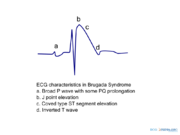

| 09:21, 9 October 2012 | Brugada ecg characteristics.png (file) |  |

39 KB | 1 | |